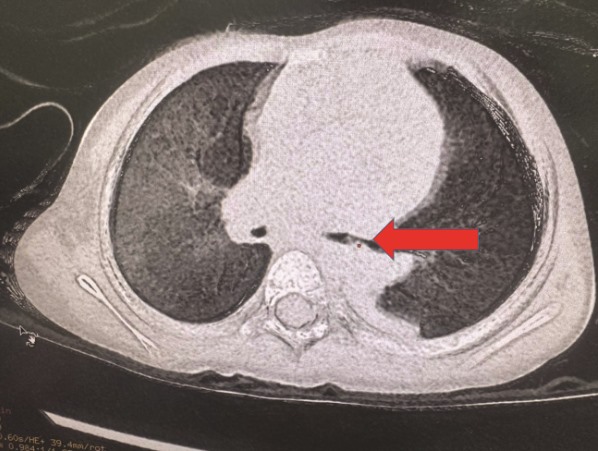

When admitted to the hospital, the patient was in a deep coma (3 points in glasgow), had weak light reflex, no pulse, and blood pressure could not be measured. Doctors immediately performed emergency cardiopulmonary resuscitation: Peristaltic heart attack, Adrenalin injection and breathing tube pose. During the Tube placement, the doctors discovered that the foreign object that caused the airway obstruction was rice grains at dinner. After 20 minutes of effort, the patient had a pulse back.